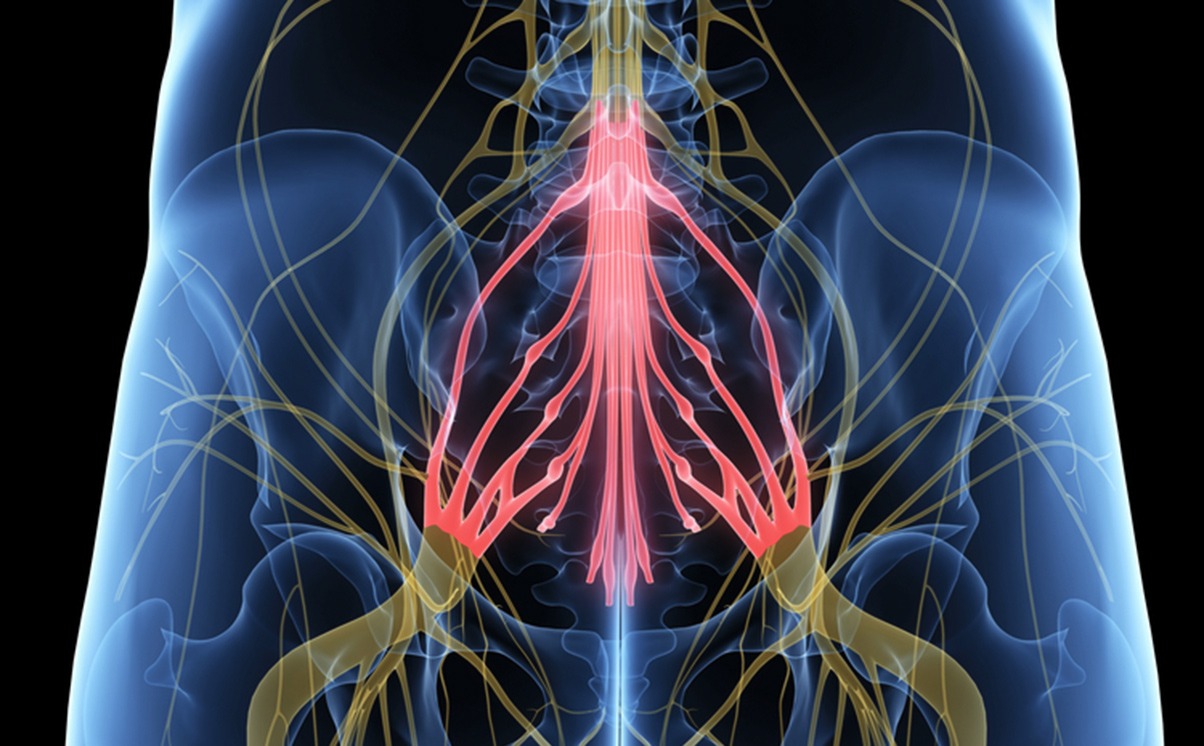

KT’s husband called an ambulance, which took over four hours to arrive. KT was eventually taken back to her local hospital that morning. It was noted that KT had still not passed urine since the previous day and that she had a number of red flag symptoms indicating serious spinal pathology including bilateral sciatica and reduced anal tone. A telephone call was made to the neurosurgery department at a specialist London NHS hospital and the advice was to do an MRI scan the following morning.

On 29 September 2014, an MRI scan reported an L4-5 disc prolapse. Despite this finding and KT’s worsening condition, no further action was taken for several days. During this period, KT lost all power in her right foot and lost control of her bowels.

KT was left with incomplete paraplegia. Her most significant injury was her severe right foot drop which caused her difficulty walking and going up and down stairs. KT required crutches to walk and a wheelchair for long distances. KT suffered from neuropathic pain as well as bladder, bowel and sexual dysfunction. She was unable to return to her work and she experienced depression. Her husband became her main carer.

Independent expert evidence was obtained from doctors specialising in emergency medicine, neurosurgery and a paramedic. All of the experts were critical of the delays in treating cauda equina syndrome, which is a medical emergency requiring immediate surgery.